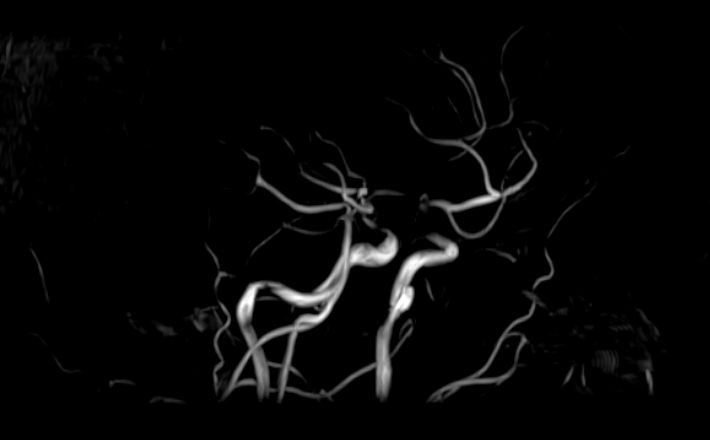

МР-ангиография — неинвазивный безопасный метод исследования для диагностики патологии сосудистой системы головы и шеи. Магнитно-резонансная ангиография позволяет получить трехмерное изображение кровеносных сосудов, оценить анатомическое строение сосудистой системы головного мозга и функциональные особенности кровотока.

С помощью электромагнитных волн томограф послойно сканирует структуры исследуемого органа, затем посредством компьютерных программ преобразует полученные данные в трехмерное изображение. При этом на снимке видна только сосудистая система без окружающих тканей. Таким образом, сканирование в режиме ангиографии позволяет визуализировать артерии и вены головного мозга без контрастирования. Однако в некоторых случаях для более точной диагностики может потребоваться введение контраста. Для этого используются гадолиний содержащие контрастные вещества. Дополнительное контрастирование дает возможность визуализировать мельчайшие сосуды и выявить нарушения микроциркуляции головного мозга.